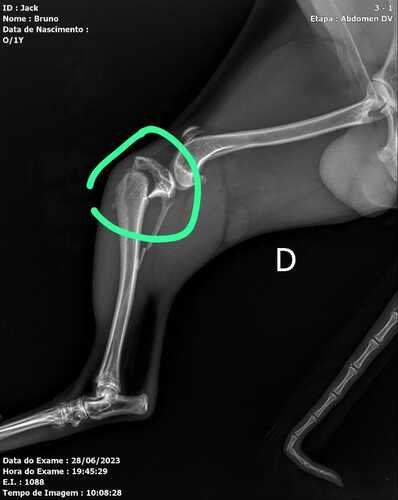

Eu sou Bruno, pai do Jake que é um doguinho de 11 meses muito alegre, carinhoso e amoroso, e muito muito espuleta, no dia 28/06/2023 Jake se machucou sozinho, e acabou fraturando as duas pernas traseiras, sendo assim precisando passar por cirurgia.Por isso estamos aqui pedindo ajuda pra quem puder doar qualquer valor para que o Jake volte a correr e brincar